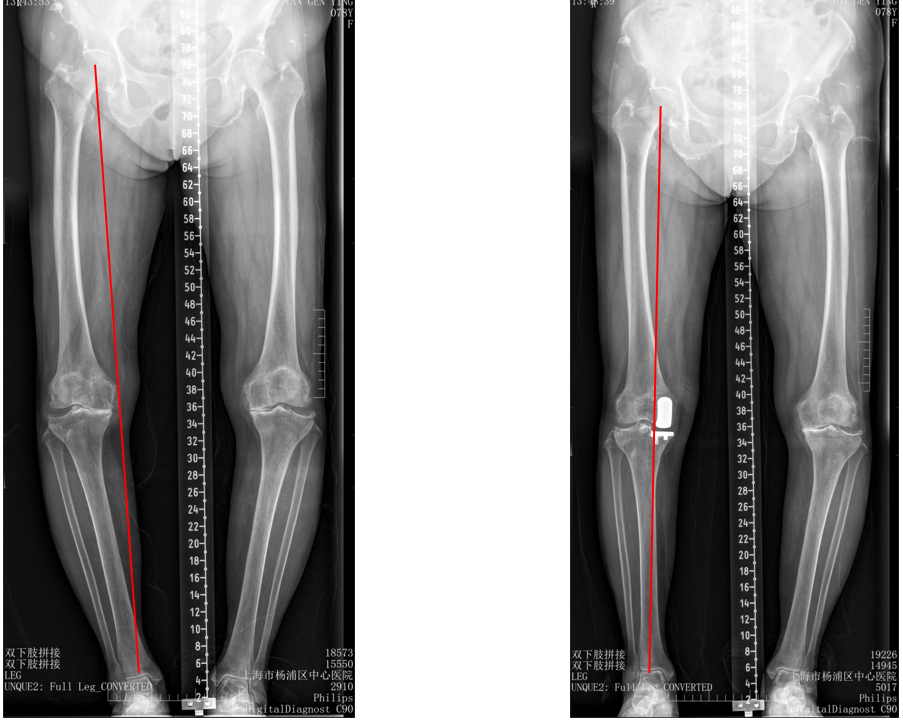

二、外侧SIGMA:registered: HP KNEE假体位置

标准胫骨假体位置

AP位胫骨与股骨假体位置:胫股角10°,轻度膝外翻;水平截骨轻度外翻,外侧缘与胫骨平台外侧缘齐平; 股骨假体中轴线与胫骨假体垂直,股骨假体中心与胫骨假体中心一致。

侧位片胫骨与股骨假体位置:胫骨假体后倾7°,前后缘齐平;股骨假体后倾15°;股骨远端截骨面与股骨髓腔中心线垂直,完整包容股骨后髁。

外侧间隙过分填塞(膝内翻)

AP位胫骨与股骨假体位置:胫股角-2°,膝内翻;屈曲间隙过份填塞,关节线上移,股骨假体外翻。